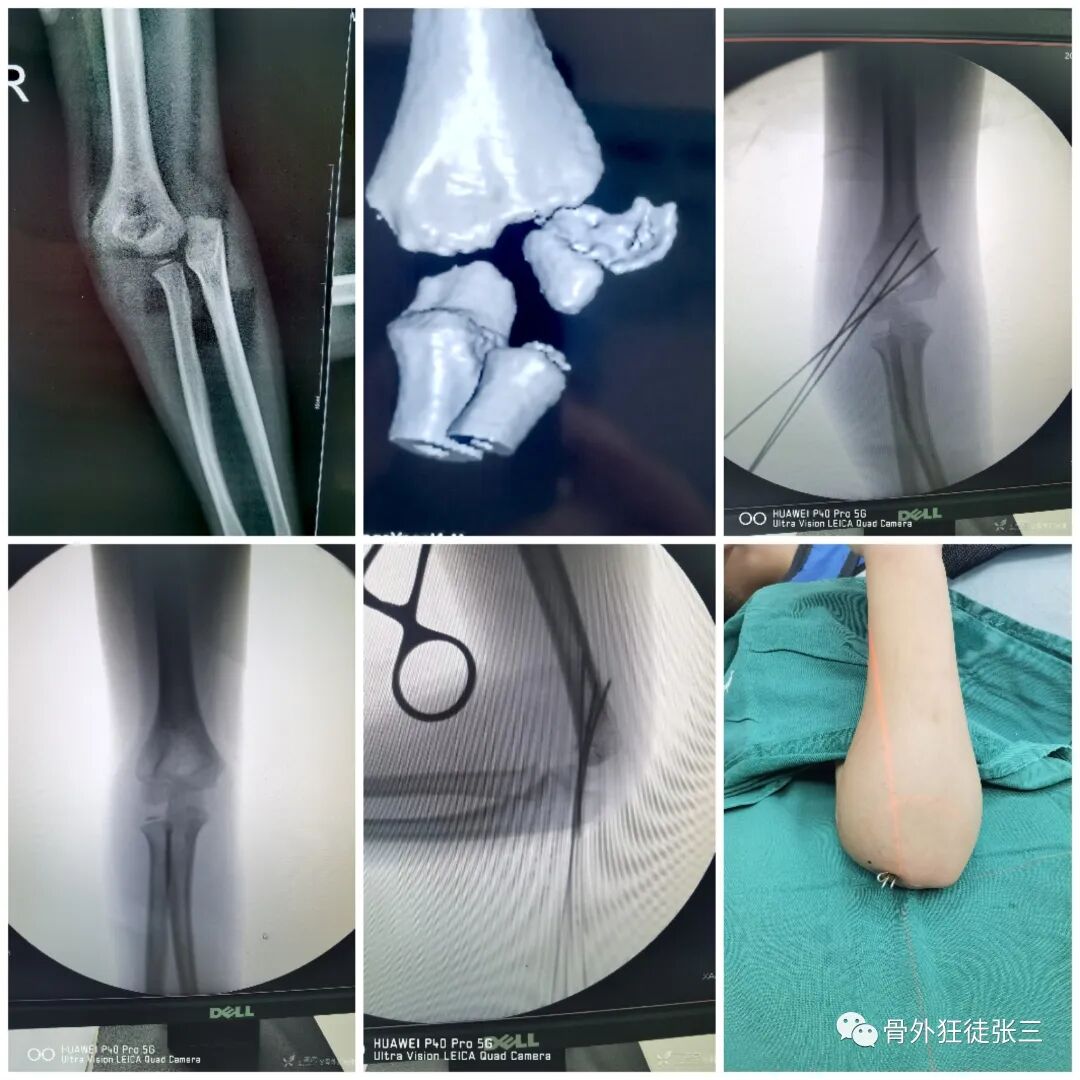

病例14,儿童髁上骨折零切开,桡侧三枚针发散固定

病例15,儿童髁上骨折零切开,

病例16,儿童髁上骨折零切开

病例17,低位髁上骨折零切开

病例18,第一掌骨基底部骨折,闭合复位,克氏针支架